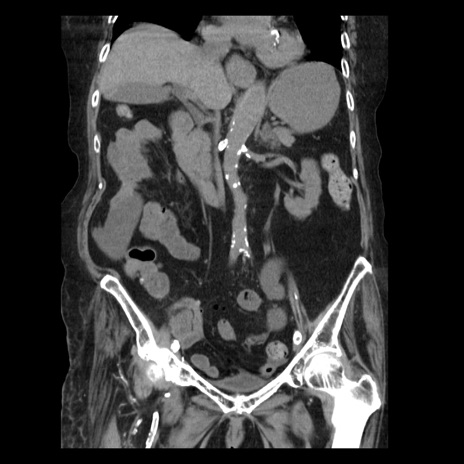

症例14(冠状断像)

【症例】 90歳代女性

【主訴】 腹痛・嘔吐

【現病歴】今朝から左側腹部痛を認めた。 経過観察していたが、嘔吐を認めたため来院。

【既往歴】 子宮癌術後

【身体所見】 意識清明、BP 127/54mmHg、P 98bpm Sp02 95%(RA)、BT 35.8°C、腹部平坦・軟腸ぜん動音聴取良好、右下腹部圧痛(+) 反跳痛なし

【データ】WBC 9800、CRP 0.46